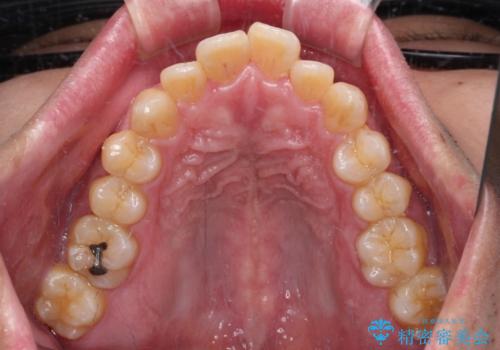

- 口が閉じられないとのことで来院された患者様です。

顎先に力を入れないと唇が閉じきれない口元であったので、上下左右の第一小臼歯4本を抜歯して、ワイヤー装置にて矯正治療を行うこととしました。